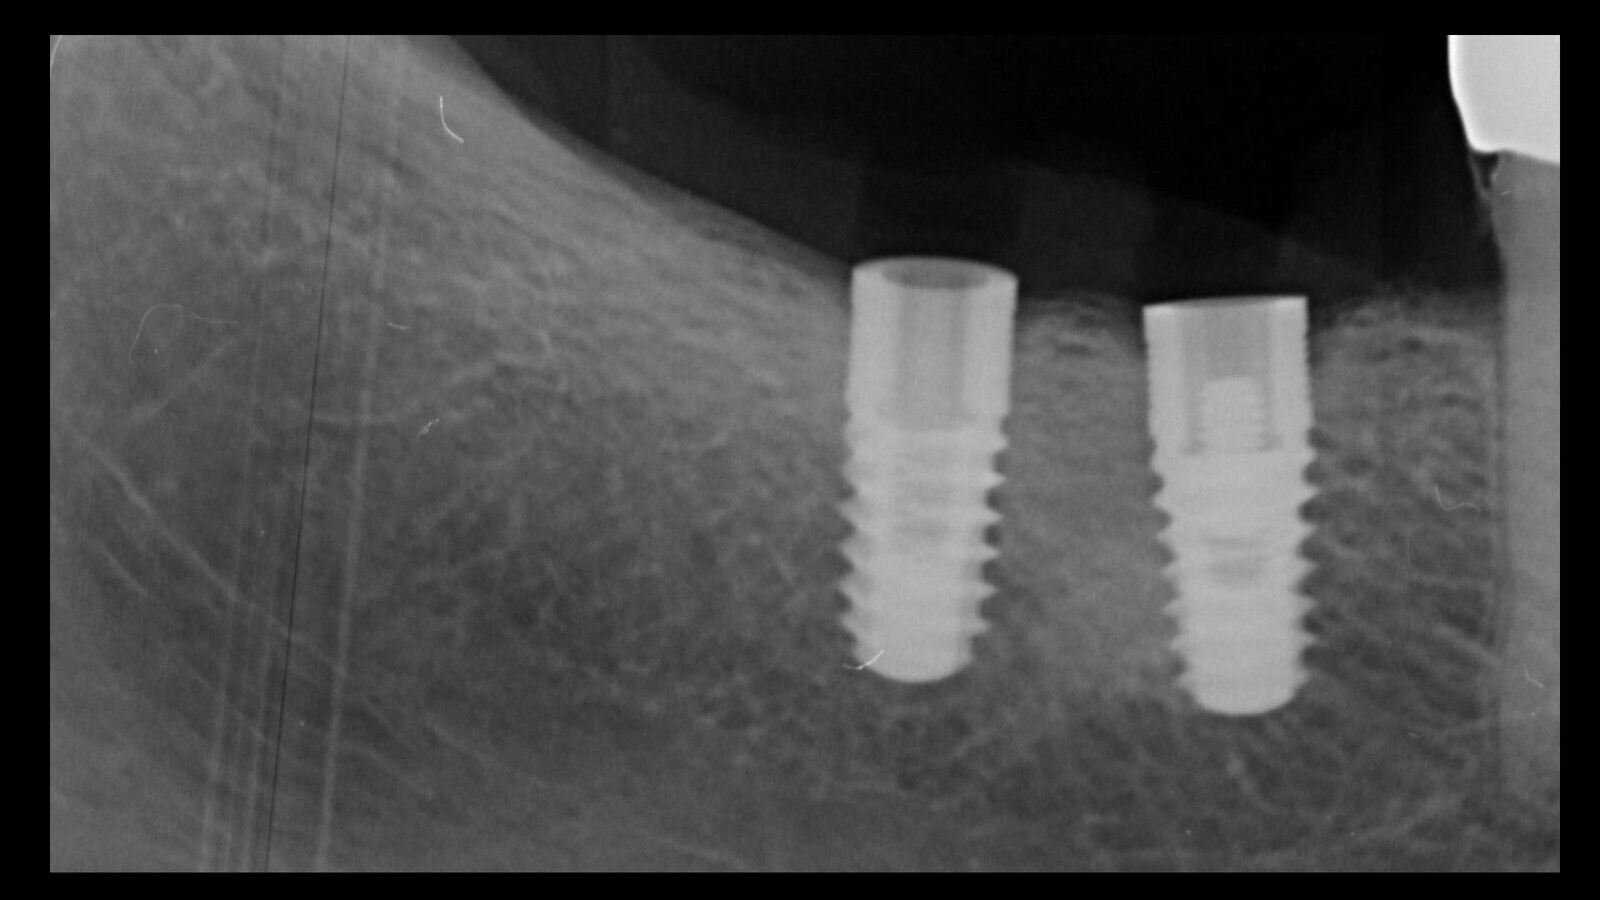

Figura 3. Esta intuición fue confirmada por el examen radiográfico, que mostró claramente el fragmento del tornillo separado dentro del implante.

Figura 11. La radiografía muestra que se realizó una remoción limpia del implante.